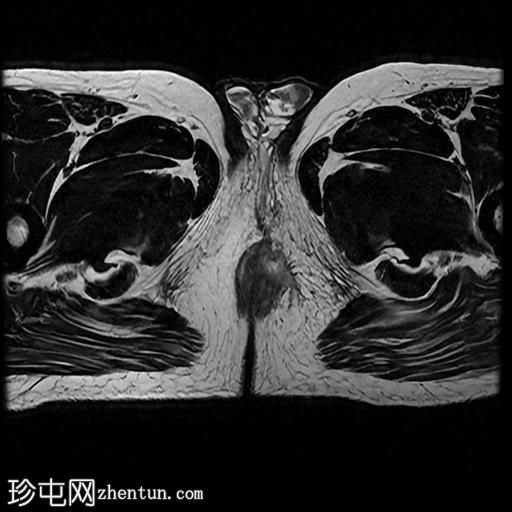

MRI

轴向位

T2

轴向位T2

脂肪饱和度

T1

轴向位T1

冠状位T1

冠状位

冠状位T2

C+脂肪饱和度

一条68毫米厚的强化通道始于左侧肛周区域,向上穿过肛门内外括约肌,在2点钟方向开口于肛管。

无脓肿形成。

MRI成像特征与所述左侧经括约肌肛周瘘相符。